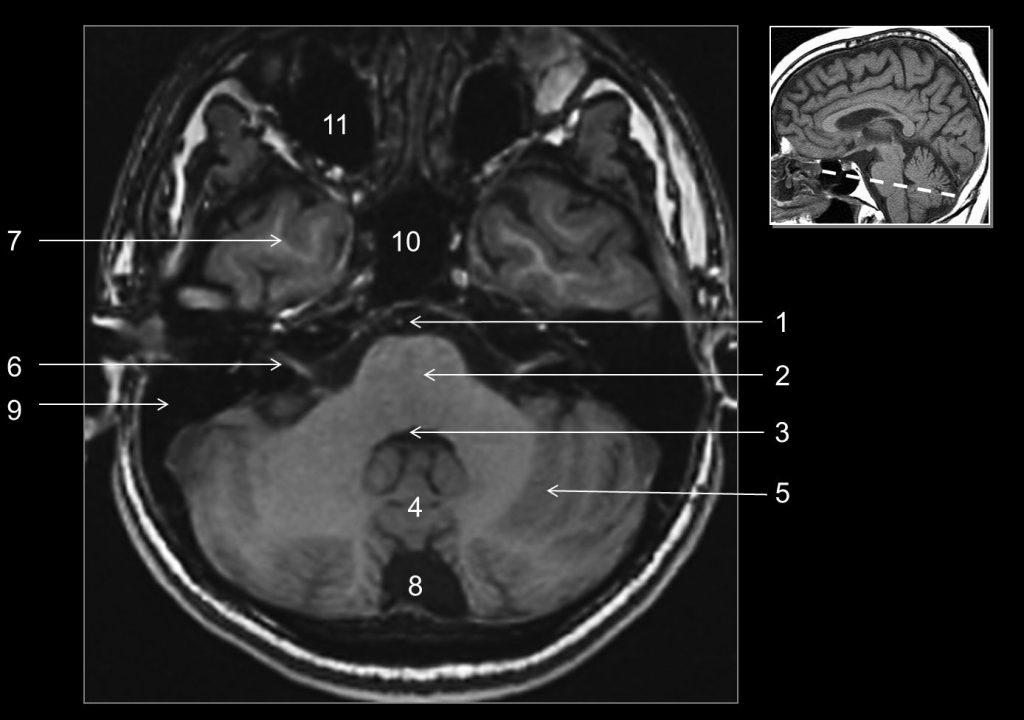

Fig. 48.4 Coupe axiale (IRM) en pondération T1 : pont.

1. Artère basilaire. 2. Pont. 3. Quatrième ventricule. 4. Vermis. 5. Hémisphère cérébelleux. 6. Nerfs facial (VII) et vestibulocochléaire (VIII). 7. Lobe temporal. 8. Citerne cérébello-médullaire. 9. Rocher. 10. Sinus sphénoïdal. 11. Sinus maxillaire.